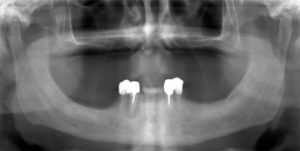

Unterkiefer

Im Februar wurden die Zähne 43 und 44 gezogen (links auf dem Röntgenbild), am selben Tag wurde eine vorläufige metallfreie Kunststoffprothese der Marke DEFLEX gefertigt. Ende Mai 2012 wurde eine herausnehmbare IVOCLAR-Stegprothese auf zwei Teleskopkronen gesetzt.